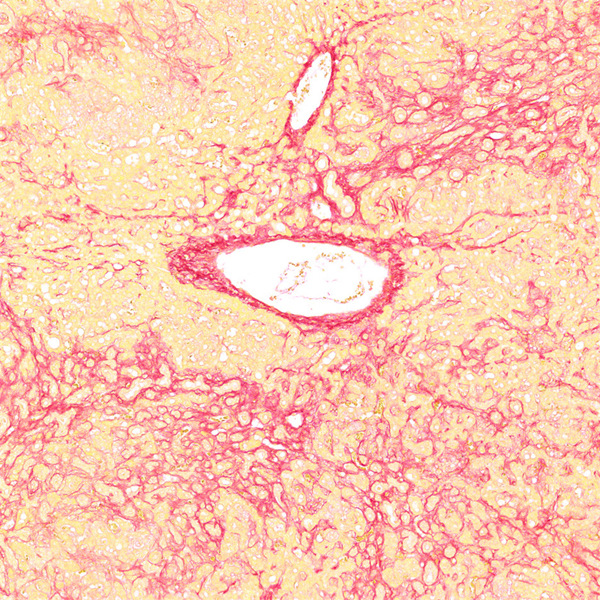

未脱钙骨组织切片经天狼猩红染色后,在普通光学显微镜下观察,胶原纤维呈现红色或鲜红色,其余组织成分呈黄色;在偏振光显微镜下观察,Ⅰ 型胶原纤维呈现强橙黄色或亮红色,Ⅲ 型胶原纤维则呈现绿色。